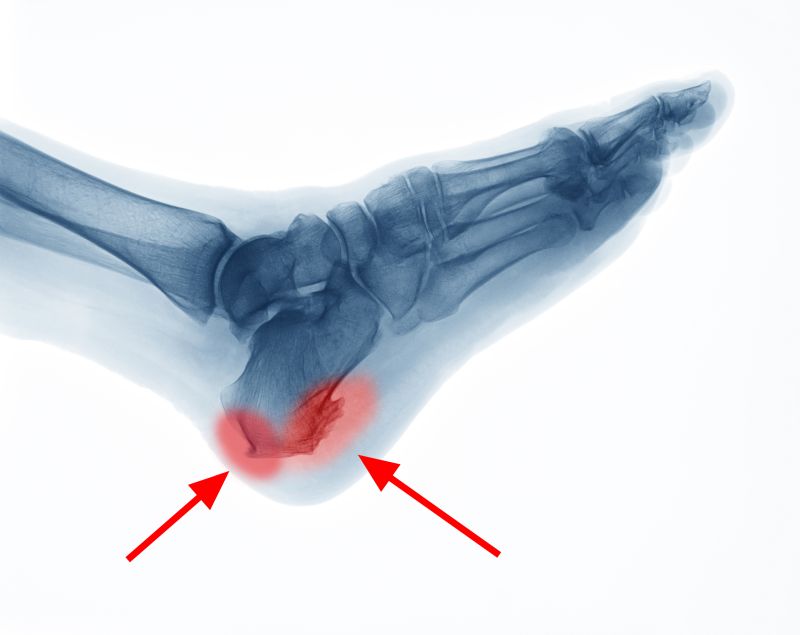

- Sarkantyú leggyakrabban a sarokcsonton, az Achilles-ín tapadási pontján alakul ki valamilyen tartós túlterhelés következtében, tehát sohasem!!! véletlenül jelenik meg az a bizonyos fájdalmas meszes kinövés

- sőt, ha hosszú ideig fennáll a túlterhelés, a szervezet védekező mechanizmusként még meg is erősíti azt a bizonyos tapadási pontot, azaz plusz csontot növeszt annak érdekében, hogy megnövelje és stabilabbá tegye az Achilles tapadási pontát. Így alakul ki a sarkantyú vagy a Haglund sarok